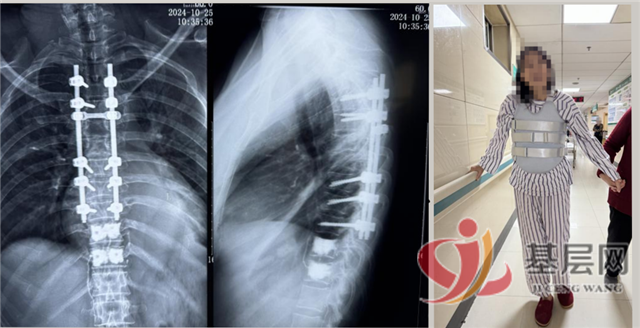

针对这一情况,骨一科付敏主任迅速组织多学科联合会诊,为杨阿姨制定了一套合理的治疗方案。在获得患者及家属的知情同意后,经过充分准备,付敏主任团队成功为患者实施了T5-8椎体骨折切开复位钉棒内固定术、T5、6椎板切除及椎管扩大减压术、以及T10、11椎体成形术。在骨一科医护人员的共同努力下,术后杨阿姨的病情逐渐好转,现已能够正常行走。